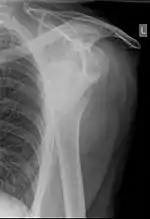

| دررفتگی شانه راست (حفره گودی-کاسهای استخوان کتف خالی است. | |